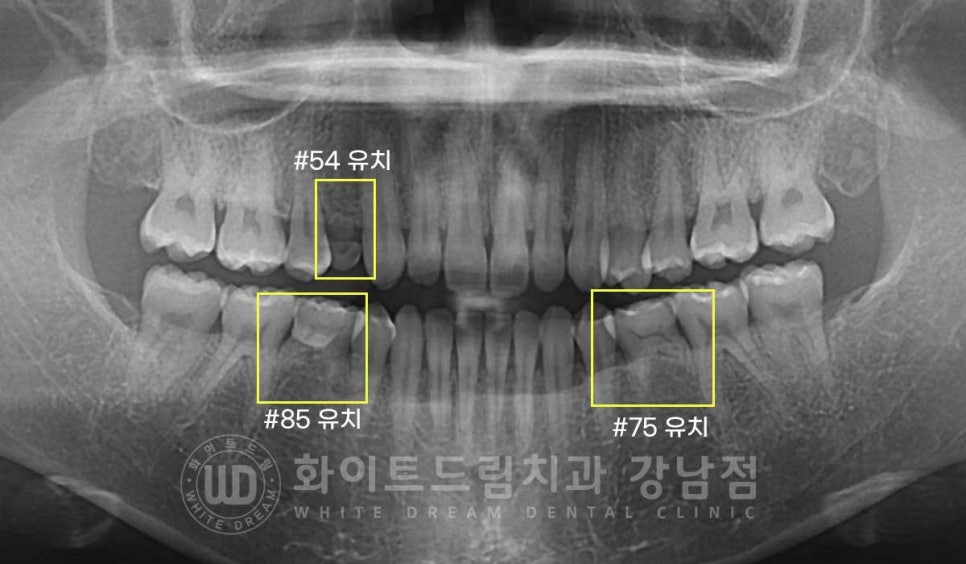

오늘 소개해 드릴 환자분의 x-ray 사진을 보면

상악 14번 소구치, 하악 35, 45번 소구치가 결손된 상태로

해당 결손치 부위는 유치가 남아있는 상태입니다.

환자분은 3개의 유치들 중 상악에 위치하고 있는 54번 유치가 심하게 흔들리고 있어

이를 발치한 후 임플란트를 식립한 case입니다.

▲ 가뜩이나 작은 치아인데 치아 뿌리도 많이 흡수되어 치아가 더 작아 보입니다.